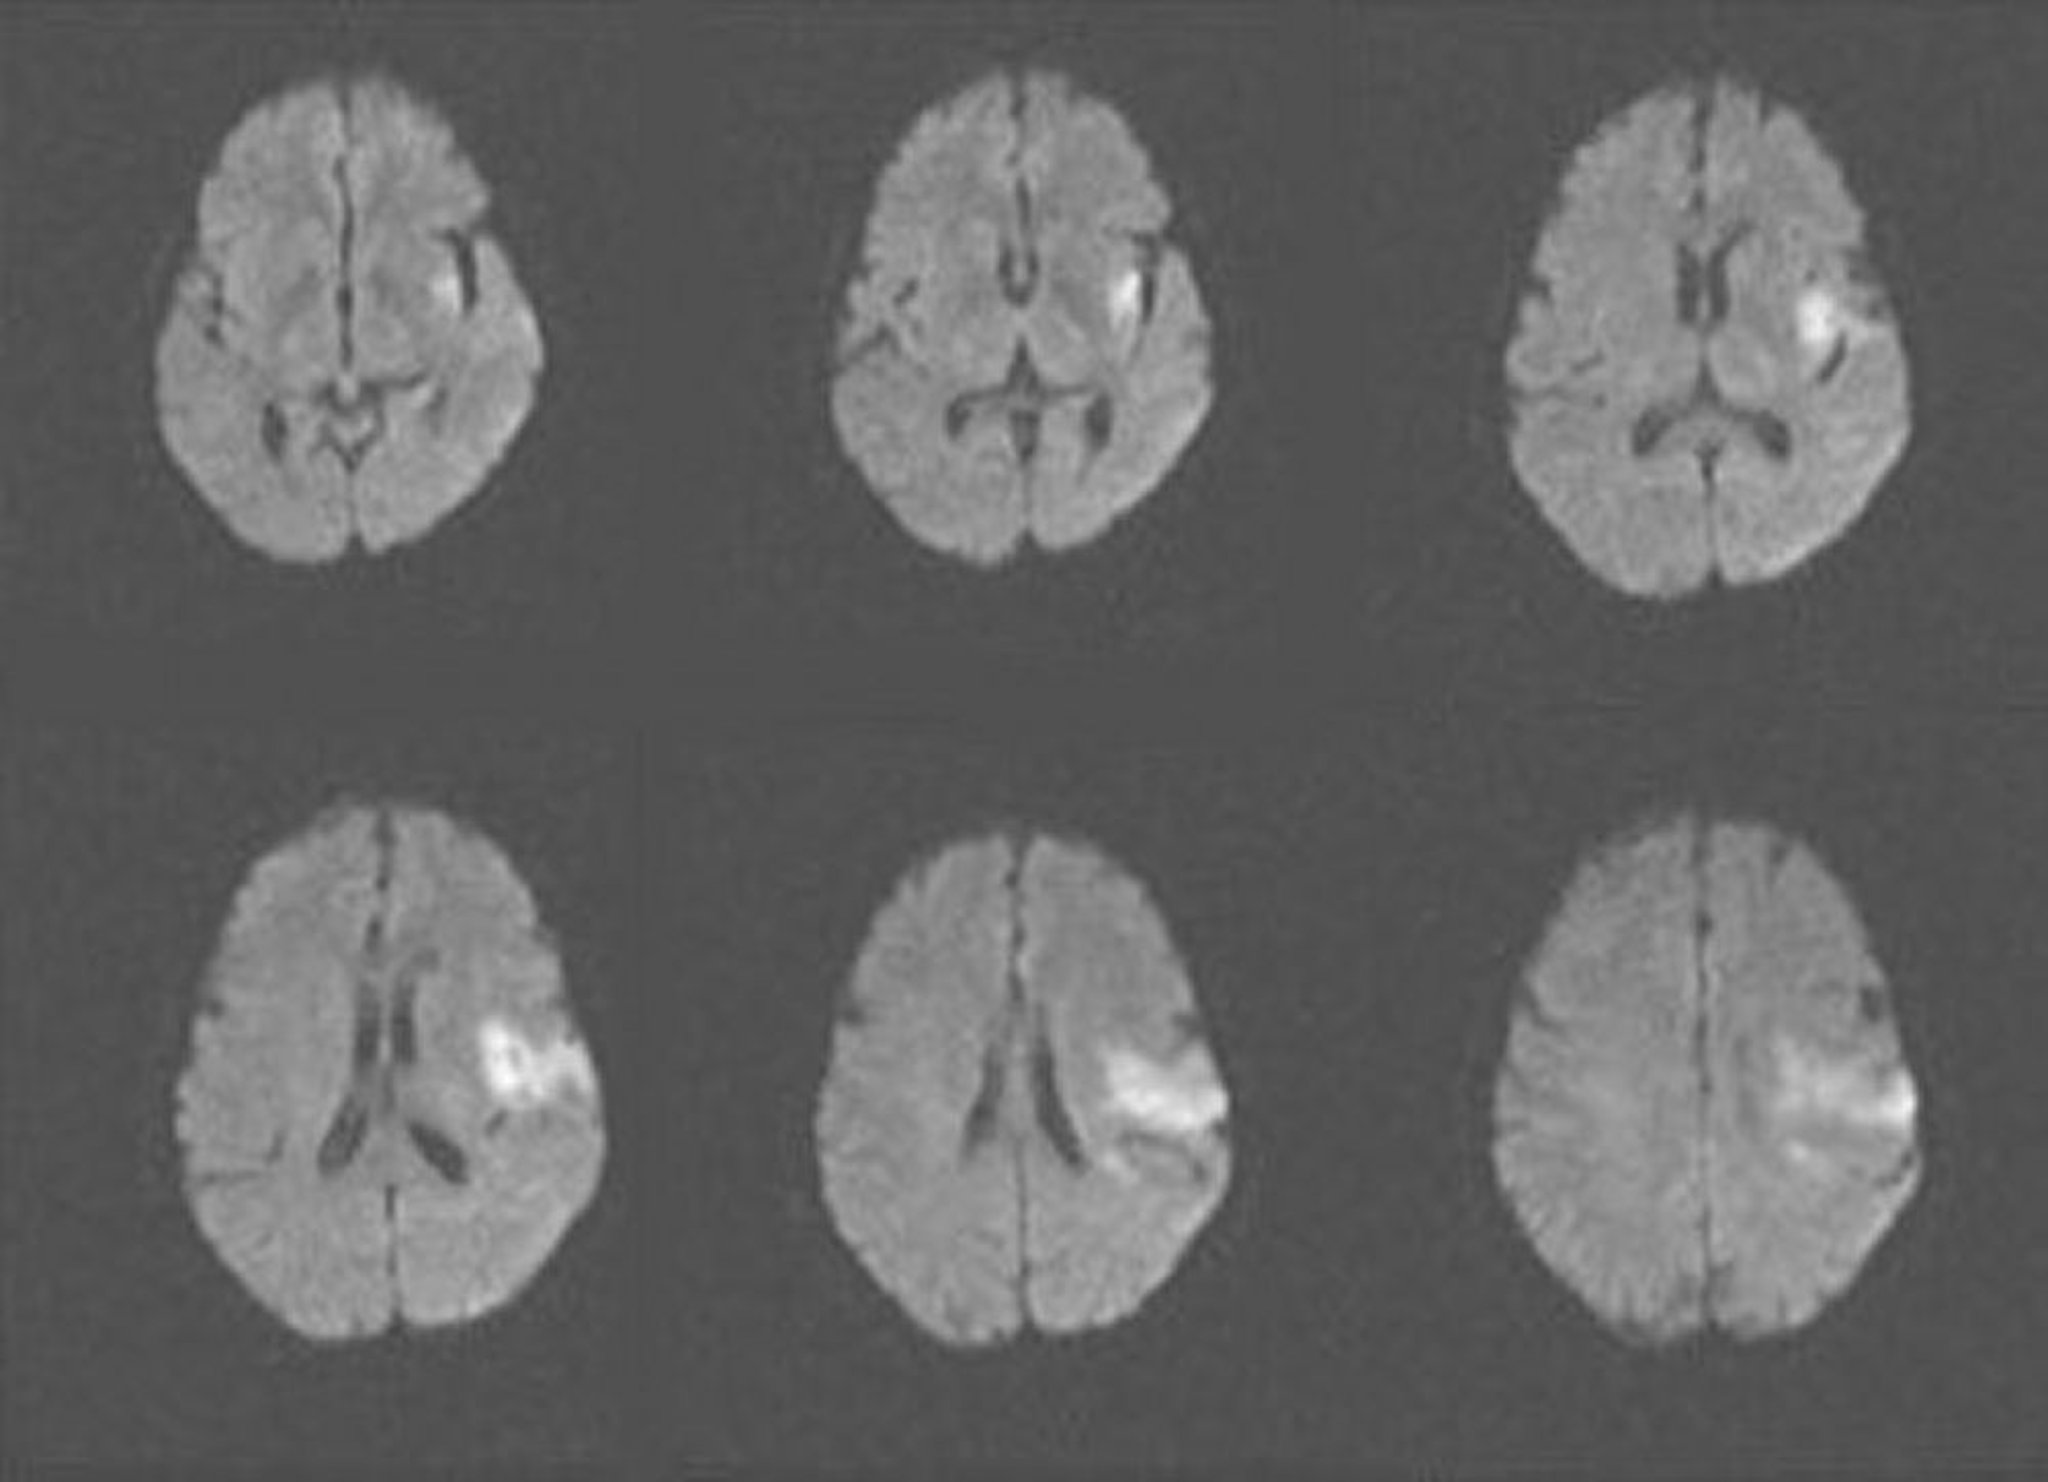

Accident vasculaire cérébral ischémique aigu (IRM)

Cette IRM montre une zone de diffusion restreinte compatible avec un accident vasculaire cérébral ischémique aigu des lobes insulaires et frontaux gauches.

Image courtoisie de Ji Y. Chong, MD.